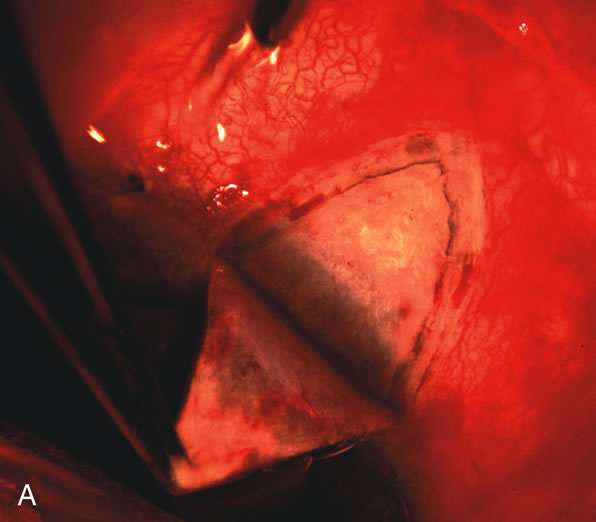

Fig. 1. The anatomic advantage of small incision cataract surgery for the glaucoma patient. A. Long-term bleb function with a large cataract incision is difficult to achieve with either ECCE-trabeculectomy or trabeculectomy followed later by ECCE. This bleb failed to form sufficiently when combined with large incision ECCE. The inflammation, bleeding, and long-term wound healing with stimulation of fibroblasts associated with this technique are more likely to cause bleb failure. In addition, the increased iris manipulation necessary to deliver the nucleus and subsequent iris repair adds to the long-term breakdown of the blood aqueous barrier. B and C. Two-site phacotrabeculectomy has the advantage of small incision cataract surgery combined with separate site trabeculectomy. The incision size is one third the size of the standard ECCE. The inflammation is less severe, and cataract wound healing is confined to the temporal area. Visual rehabilitation with phacoemulsification and foldable IOL is much faster. Phacoemulsification allows successful lens extraction even in the unfriendly environment of a smaller pupil compared with ECCE. The trabeculectomy is performed in an entirely different site, well away from the wound healing associated with temporal phacoemulsification. The likelihood of this filter functioning long-term is greater than with ECCE-trabeculectomy. D. The surgeon also has the option of single-site phacotrabeculectomy with foldable IOL. Both the lens extraction and trabeculectomy are performed through one small 3.5-mm limbal incision.